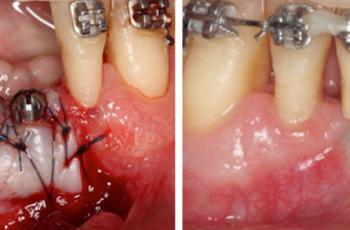

Tratamiento no quirúrgico de la periimplantitis. A propósito de un caso... Cirugía periodontal y periimplantaria | UIC Tratamiento no quirúrgico de la periimplantitis. A propósito de un caso... Se presenta el caso de una paciente de 58 años de edad, sin antecedentes médicos de interés y no fumadora. El motivo... Etiología, diagnóstico y tratamiento de la periimplantitis: Caso... Tto. Periimplantario | UV Etiología, diagnóstico y tratamiento de la periimplantitis: Caso... Presentamos nuevo caso clínico realizado por los doctores Manuel Rodríguez Aranda, Francisco... Efectividad del Tratamiento en Periodontitis Agresiva Tto. Periodontal | UIC Efectividad del Tratamiento en Periodontitis Agresiva El mantenimiento de la dentición natural en estado de salud ha sido un objetivo importante en... Injerto gingival libre alrededor de implantes dentales. A propósito de un... Cirugía periodontal y periimplantaria | UIC Injerto gingival libre alrededor de implantes dentales. A propósito de un... La cirugía mucogingival reconstructiva alrededor de implantes corrige los defectos de la... Terapia mucogingival en implantes: corrección de las secuelas mucosas de... Cirugía periodontal y periimplantaria | UV Terapia mucogingival en implantes: corrección de las secuelas mucosas de... El caso que se presenta a continuación muestra una resolución impecable de un defecto mucogingival... Importancia del mantenimiento en la evolución de un paciente con... Mantenimiento | UV Importancia del mantenimiento en la evolución de un paciente con... La periodontitis agresiva se define como una enfermedad de rápida progresión en la destrucción... Tratamiento de Recesiones Gingivales Clase III de Miller mediante técnica... Cirugía periodontal y periimplantaria | UIC Tratamiento de Recesiones Gingivales Clase III de Miller mediante técnica... El caso clínico que presentamos a continuación es el de una paciente que acude a la consulta... Tratamiento de un paciente con periodontitis crónica moderada generalizada Tto. Periodontal | UIC Tratamiento de un paciente con periodontitis crónica moderada generalizada El caso clínico que se presenta a continuación, muestra el tratamiento de una paciente...